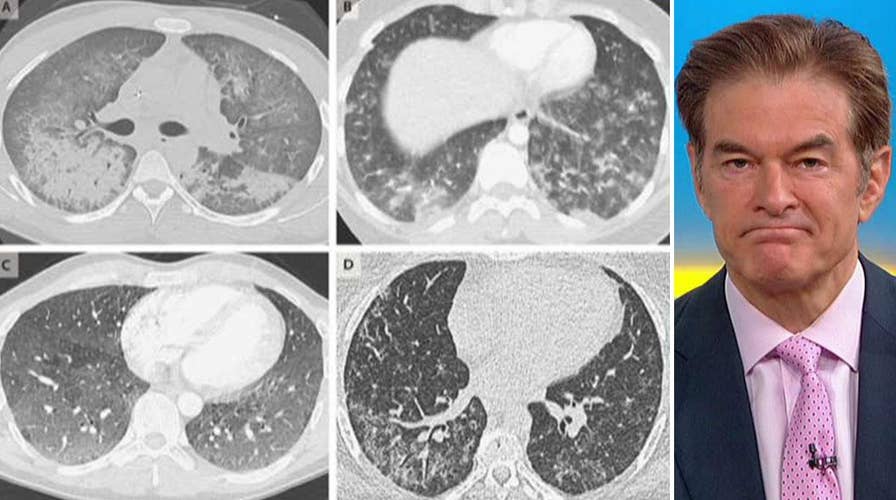

Dr. Mehmet Oz reacts to another person dying from a mysterious vaping-related illness and opens up on his mother's recent Alzheimer's diagnosis on 'Fox & Friends.'